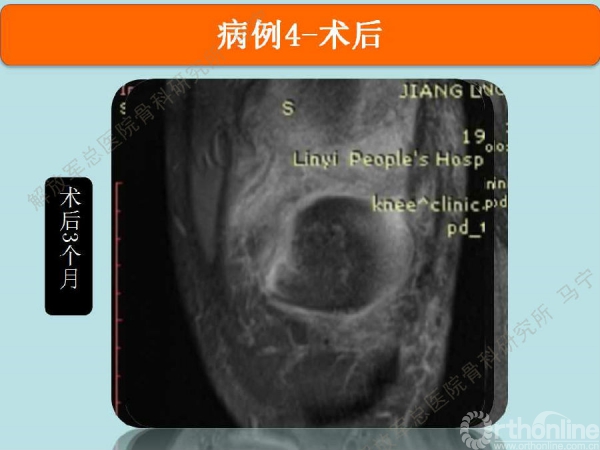

术后3个月在当地医院复查MRI,软骨补片与正常软骨还存在GAP现象,冠状位隐约还能看见周围的轮廓。